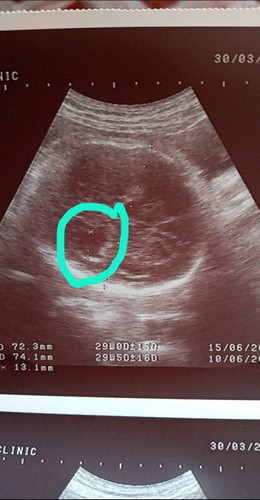

ช่องว่างในสมองผิดปกติ

ซาวมาทุกเดือนลูกแข็งแรงสมบูรณ์ดีมาก พอมาถึงวันนัดตามปกติ32สัปดา5วัน ไปซาวอีกหมอพอ ช่องในสมองกว้างผิดปกติ จนจะคลอดแล้วทำไมพึ่งเจอ แล้วมาบอกว่าแก้ใขไรไม่ทันแล้ว ต้องรอคลอดออกมา เราอาจจะไม่ไดเลี้ยงเขาตลอดชีวิด